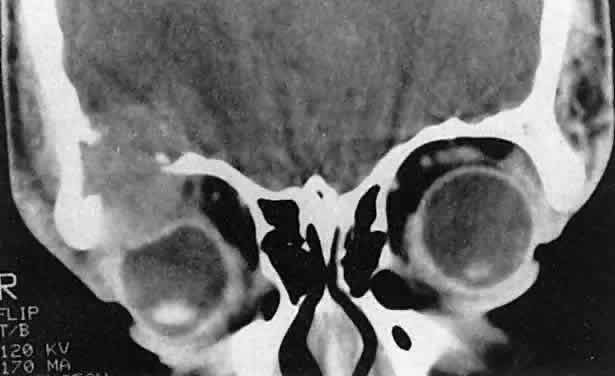

Dermoid cysts are most often encountered at the frontozygomatic articulation but can occur at other suture lines, including those deep in the orbit. Most lesions are anterior and paraorbital (Fig. 19), located between the orbicularis muscle and the periosteum overlying the orbital rim, and have a fibrous stalk to the suture line. Anterior cysts produce minimal bone change. Other lesions may be entirely intraorbital, causing proptosis and globe displacement. Their expansion produces an overall increase in orbital volume as well as local bone changes (Fig. 20). Dermoid and epidermoid cysts also may be largely intradiploic, with expansion into the anterior cranial fossa, the temporal fossa, or the orbit. Dumbbell lesions may be present with narrow intraosseous components.

Fig. 20. A. Right proptosis was noted only a few weeks before presentation in this 3-year-old girl. B. A long-standing process is suggested by overall expansion of the bony orbit and local fossas on the orbital faces of the zygomatic and sphenoid bones. Keratin clumps and glandular products within the dermoid cyst have different radiodensities.

Anterior, paraorbital dermoid cysts usually are evident soon after birth. Deeper lesions may not declare themselves until mid- or late childhood, or even the adult years. Expansion of the cysts generally is slow and linear, reflecting continuous desquamation of keratinizing epithelium. There may be a point at which the pressure within the cyst inhibits further proliferation and sloughing of epithelial cells, accounting for the clinically observed stability of many lesions. Sporadic enlargement may be caused by hormonally influenced sebaceous gland secretion or by rupture of the cyst wall with a granulomatous inflammatory response to the cyst contents (see Figs. 19B-D). Such episodic change in an otherwise gradual growth pattern places intraorbital dermoid cysts into the current differential diagnosis.

Anterior lesions generally are diagnosed and removed without difficulty, although their occasional occurrence near the lacrimal excretory system can complicate treatment.89 Surgeons should strive for excision of an intact cyst, because residual epithelial elements can lead to recurrence. CT examination of deeper lesions discloses a cystic mass with some internal heterogeneity caused by the different radiodensities of keratin clumps and oily secretions (see Fig. 20B). Bone changes, from shallow fossas to spherical defects, are smooth, with a sclerotic margin and a punched-out appearance. Based on the CT findings, the differential diagnosis includes cholesterol granuloma and unifocal eosinophilic granuloma. Superomedial orbital dermoid cysts must be distinguished from meningoencephaloceles before surgical intervention.